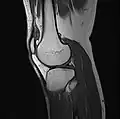

MRI

Both anterior cruciate ligament (ACL) and posterior cruciate ligaments (PCL) are hypointense on both T1 and T2 weighted images of MRI. However, some high signal striations are often seen at the distal part of the ACL, making ACL higher intensity than PCL on MRI scans.[20]

Knee MRI (PD TSE FS sagittal)

Knee MRI (T1 TSE sagittal)- Knee MRI (sagittal TSE FS)